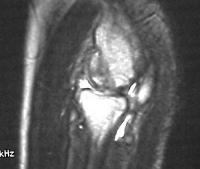

MRI shows an osteochondral sequestrum of the anterior capitellum:

Treatment options? Do nothing, Open reduction and bone graft, sequestrum excision or radial head excision. In this case, at surgery, the loose articular fragment was too thin to allow reliable fixation, and was simply excised.